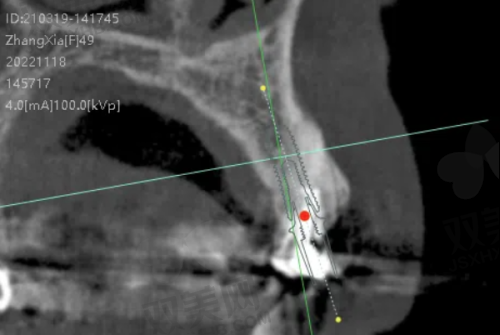

1. 数字化诊疗技术:门诊部引进了数字化口腔全景机、口腔 CT 等设备,能够快速、正确地获取患者的口腔影像信息,为诊断和治疗提供更加严谨的依据。同时,在牙齿种植和矫正等领域,采用数字化设计和制作技术,提高了治疗的精细度和成效。